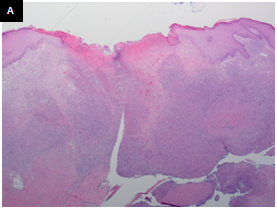

The H&E stained sections showed a dense dermal infiltrate without epidermotropism. The epidermis was ulcerated but otherwise unremarkable. The dermal lesion showed a diffuse, infiltrative growth pattern with some necrosis (Figurers 1a & 1b). Tumor foci are not surrounded by rim of small lymphocytes (Figurers 1b & 1c). At high magnification, it consisted of scattered large atypical cells in a background of mixed inflammatory cells including small lymphocytes, plasma cells, neutrophils and rare eosinophils. The atypical cells demonstrated large nuclei with vesicular chromatin, prominent inclusion-like nucleoli and ample amphophilic cytoplasm. Some of them had bilobed mirror-image nuclei. The large atypical cells were morphologically consistent with Hodgkin/Reed-Sternberg (HRS) cells and their variants (Figure 1c & 1d). Frequent mitotic Figureures, including atypical forms, are also noted (Figure 1d).

Figure 1 A. Low-power view shows a diffuse, dense dermal infiltrate with some necrosis and overlying ulcerated epidermis. B. Tumor cells demonstrate an infiltrative growth pattern, without a surrounding rim of small lymphocytes. C. The large cells are present at the base of the lesion, without a surrounding rim of small lymphocytes. D. High-power view shows large atypical cells in a background of mixed inflammation. The large cells have prominent eosinophilic nucleoli. Some of them are binucleated or multinucleated. The morphologic features are consistent with Hodgkin/Reed-Sternberg (HRS) cells and their variants. Frequent mitotic figures, including atypical forms, are noted. (H&E, A and B 20X, C 200X, D 400X).